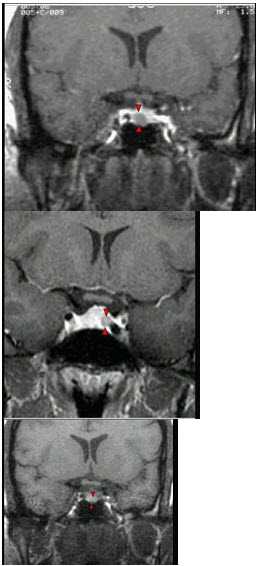

167、单项选择题

女,38岁,头痛、闭经,MRI检查如图,选择最可能的诊断()

A.垂体囊肿

B.垂体梗死

C.转移瘤

D.垂体微腺瘤

E.垂体脓肿